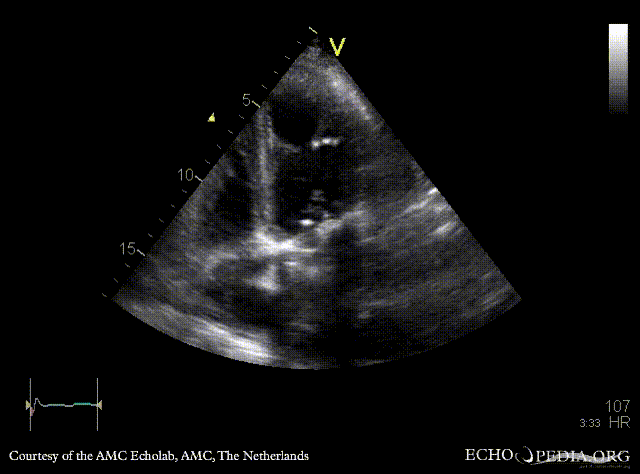

Case 108